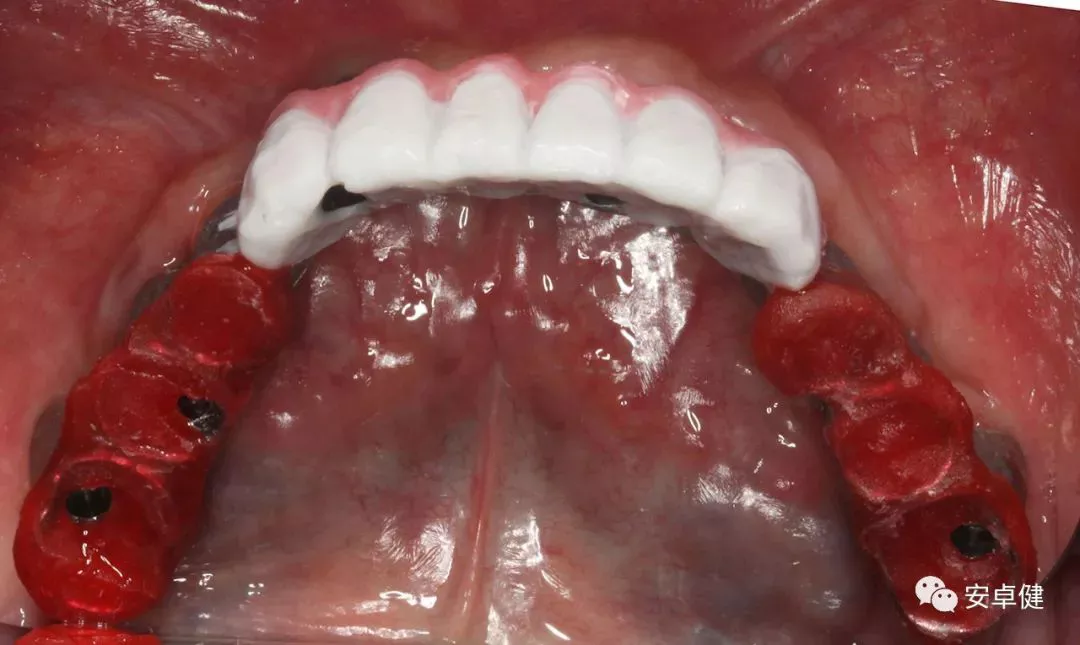

▷ 永久修复

患者术后16个月:

• 于口内试戴原厂纯钛切削一体式桥架,并检查前牙排蜡外形及后牙咬合关系;

• 聚合瓷烤塑制作最终修复体;

• 为减少牙面磨耗,于后牙区制作360度防裂纯钛金属带;

• 试戴满意后,二级螺丝加力至15N;

• 特氟龙封闭螺丝孔,光固化复合树脂封闭上方螺丝通道,完成最终固定式种植义齿修复;

• 修复体外形能够正确恢复面下1/3高度及侧貌;

• 患者可获得较为稳定的咬合关系,并满足其咀嚼功能的需求;

• 患者42、46部位牙龈退缩,缺乏足够的角化龈,为方便后期清洁维护,选择穿龈较高的龈上肩台;

• 口内观察,修复体边缘金属基台颜色暴露,但由于其处于下颌后牙非微笑暴露区,故对临床整体美观效果的影响在患者可接受范围内。